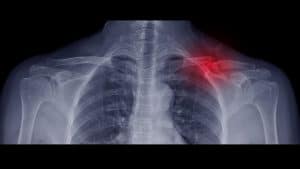

After your motorcycle accident, you should be treated for a broken clavicle as soon as possible. An X-ray will confirm that the collarbone is broken. In most cases, patients will suffer extreme pain and tenderness at the site of the break. To understand the side effects and complications of a broken collarbone, patients should understand how the specifics of their injury and treatment affect their recovery.